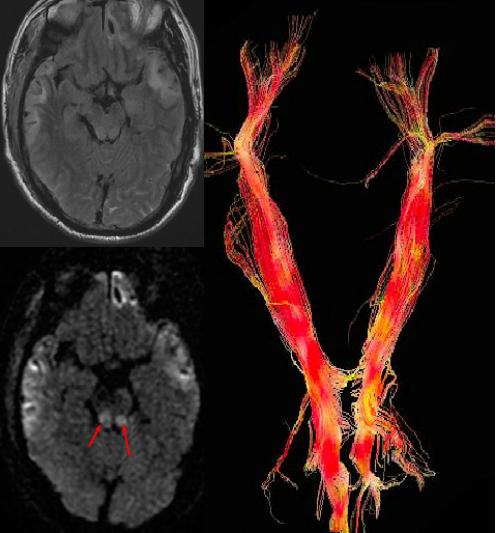

外伤患者DWI显示脑干损伤,DTT图示白质纤维束扭曲变形及移位